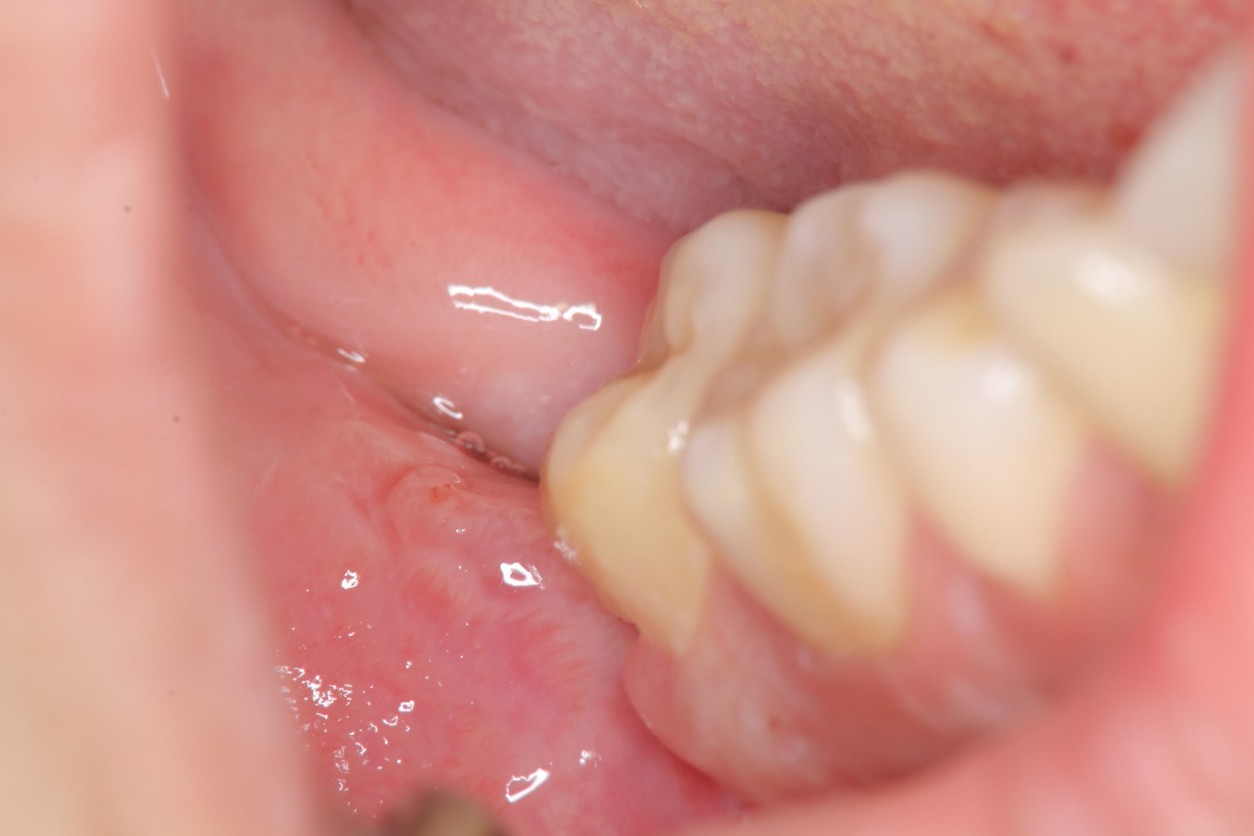

1週後傷口癒合良好